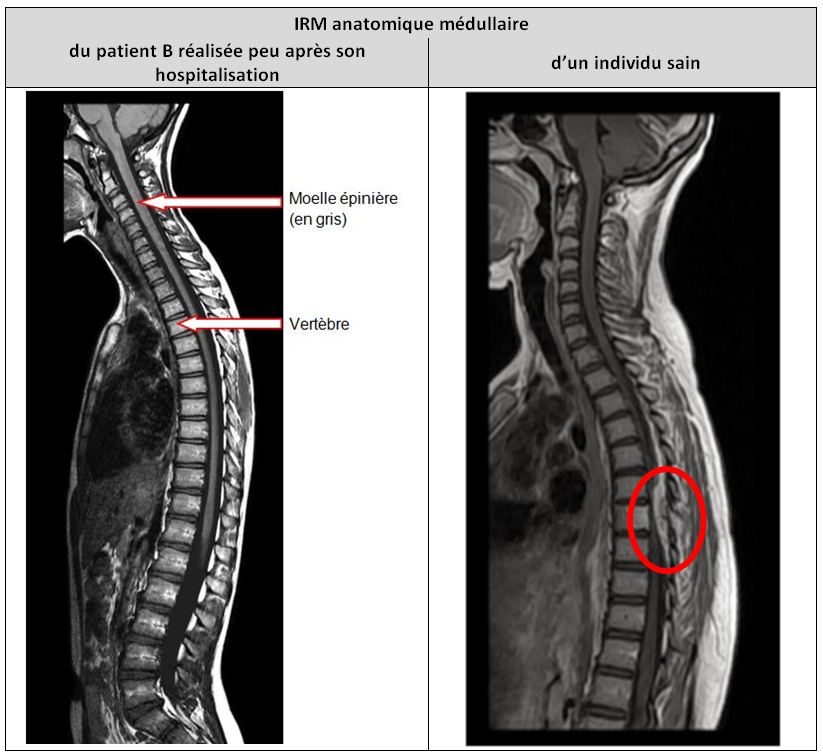

Activité pédagogique IRM médullaire + IRM cérébral et motricité

Figures et documents activité IRM médullaire + cérébral et motricité

Capture ecran production patient B.JPG